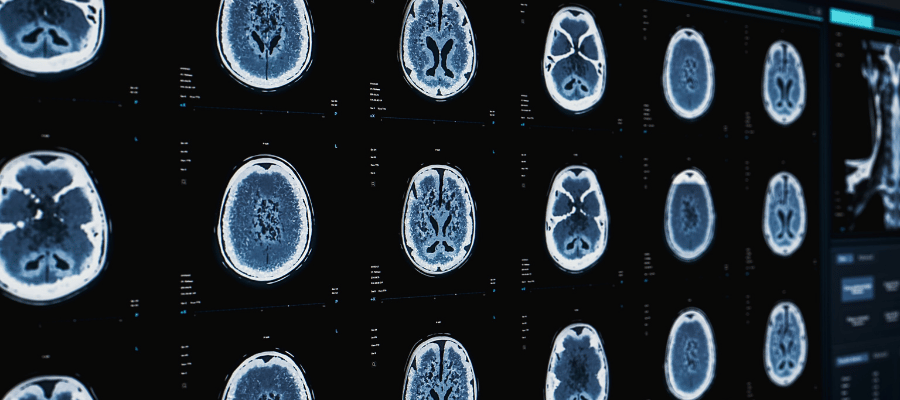

Uzun süreli stres, beyin hücreleri arasında iletişimi sağlayan nörotransmitterlerin dengesini bozabilir. Bu durum anksiyete bozuklukları, depresyon ya da hafıza problemleri gibi hastalıkların ortaya çıkmasına neden olabilir.

Ayrıca stres, beyin hacminde küçülmeye ve sinir hücrelerinin hasar görmesine yol açar. Beyin sağlığını korumak için stres yönetimi büyük önem taşır. Düzenli uyku, fiziksel aktivite ve destekleyici sosyal ilişkiler bu süreçte etkili olabilir.

Kronik stres vücudun sürekli alarm durumunda kalmasına sebebiyet verir. Bu durum, sinir sistemi üzerinde baskı oluşturarak zihinsel yorgunluğu artırır. Uzun süreli stres altında beyin yapılarında bozulmalar meydana gelebilir.

Sinir hücreleri (nöronlar) kronik stresin etkisiyle yapısal hasara uğrayabilir. Sürekli yüksek kortizol seviyeleri, nöronlar arasındaki bağlantıları zayıflatır ve bilgi iletimini yavaşlatır. Bu durum özellikle hafıza, dikkat ile öğrenme süreçlerinde belirgin sorunlara yol açar.

Hipokampus Hasarı ve Hafıza Problemleri

Hipokampus hasarı, kronik stresin beyin üzerindeki etkilerinden biri olarak hafıza problemlerine yol açabilir. Bu bölgedeki sinir hücrelerinin zarar görmesi, yeni bilgilerin öğrenilmesinde güçlük yaşanmasına neden olabilir. Zamanla bu hasar, bilişsel işlevlerde bozulmalara ve unutkanlığa yol açabilir.

Hipokampusun uzun süreli hasarı, kişilerin geçmiş deneyimlerini hatırlamada zorlanmalarına yol açabilir. Bu durum, günlük yaşamda işlevsel zorluklara neden olabilir çünkü kişisel bilgiler ve anılar zor hatırlanır. Ayrıca hafıza problemleri, stresle başa çıkma yeteneğini de etkileyerek bireylerin zihinsel sağlığını daha da olumsuz yönde etkileyebilir.

Uzun süreli stres, kortizol seviyelerinin artmasına neden olarak sinir hücrelerinin yapısını ve işlevini bozar. Özellikle hipokampus gibi hafızayla ilgili bölgelerde küçülme gözlenebilir.

Yüksek düzeyde salgılanan stres hormonları, özellikle hipokampus gibi hassas beyin bölgelerinde hücre kaybına neden olabilir. Bu zarar, öğrenme ve hafıza işlevlerinde azalma ile kendini gösterebilir.